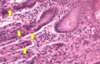

Rectum -

rectum is the terminal portion of the sigmoid colon, and therefore, it is similar in structure to the colon. At the macroscopic level, this area has longitudinal folds called rectal columns. The mucosa contains numerous goblet cells, and the submucosa may have hemorrhoidal venous plexuses which can extend into the lamina propria. The mascularis externa has

both inner circular and outer longitudinal smooth muscle layers. Arrows: some of the blood channels.